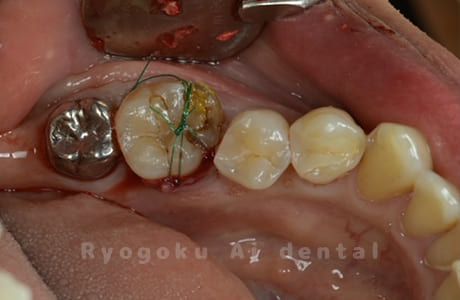

Case10

-

- 原因

- 右下6番 重度カリエス

- 治療内容

- 右下8を右下6へ移植に自家歯牙移植

- 治療期間

- 約1か月半

- 治療費用

- 220,000円

右下の銀歯が外れかかっているとのことでご来院された患者様です。虫歯が大きく、かつ歯が割れており、保存不可能と判断し、親知らずの移植を行いました。

<リスク・副作用>

治療後、痛みや違和感、出血、腫れなどが出る事があります。喫煙者、糖尿病などの方の場合、歯が生着しない場合があります。